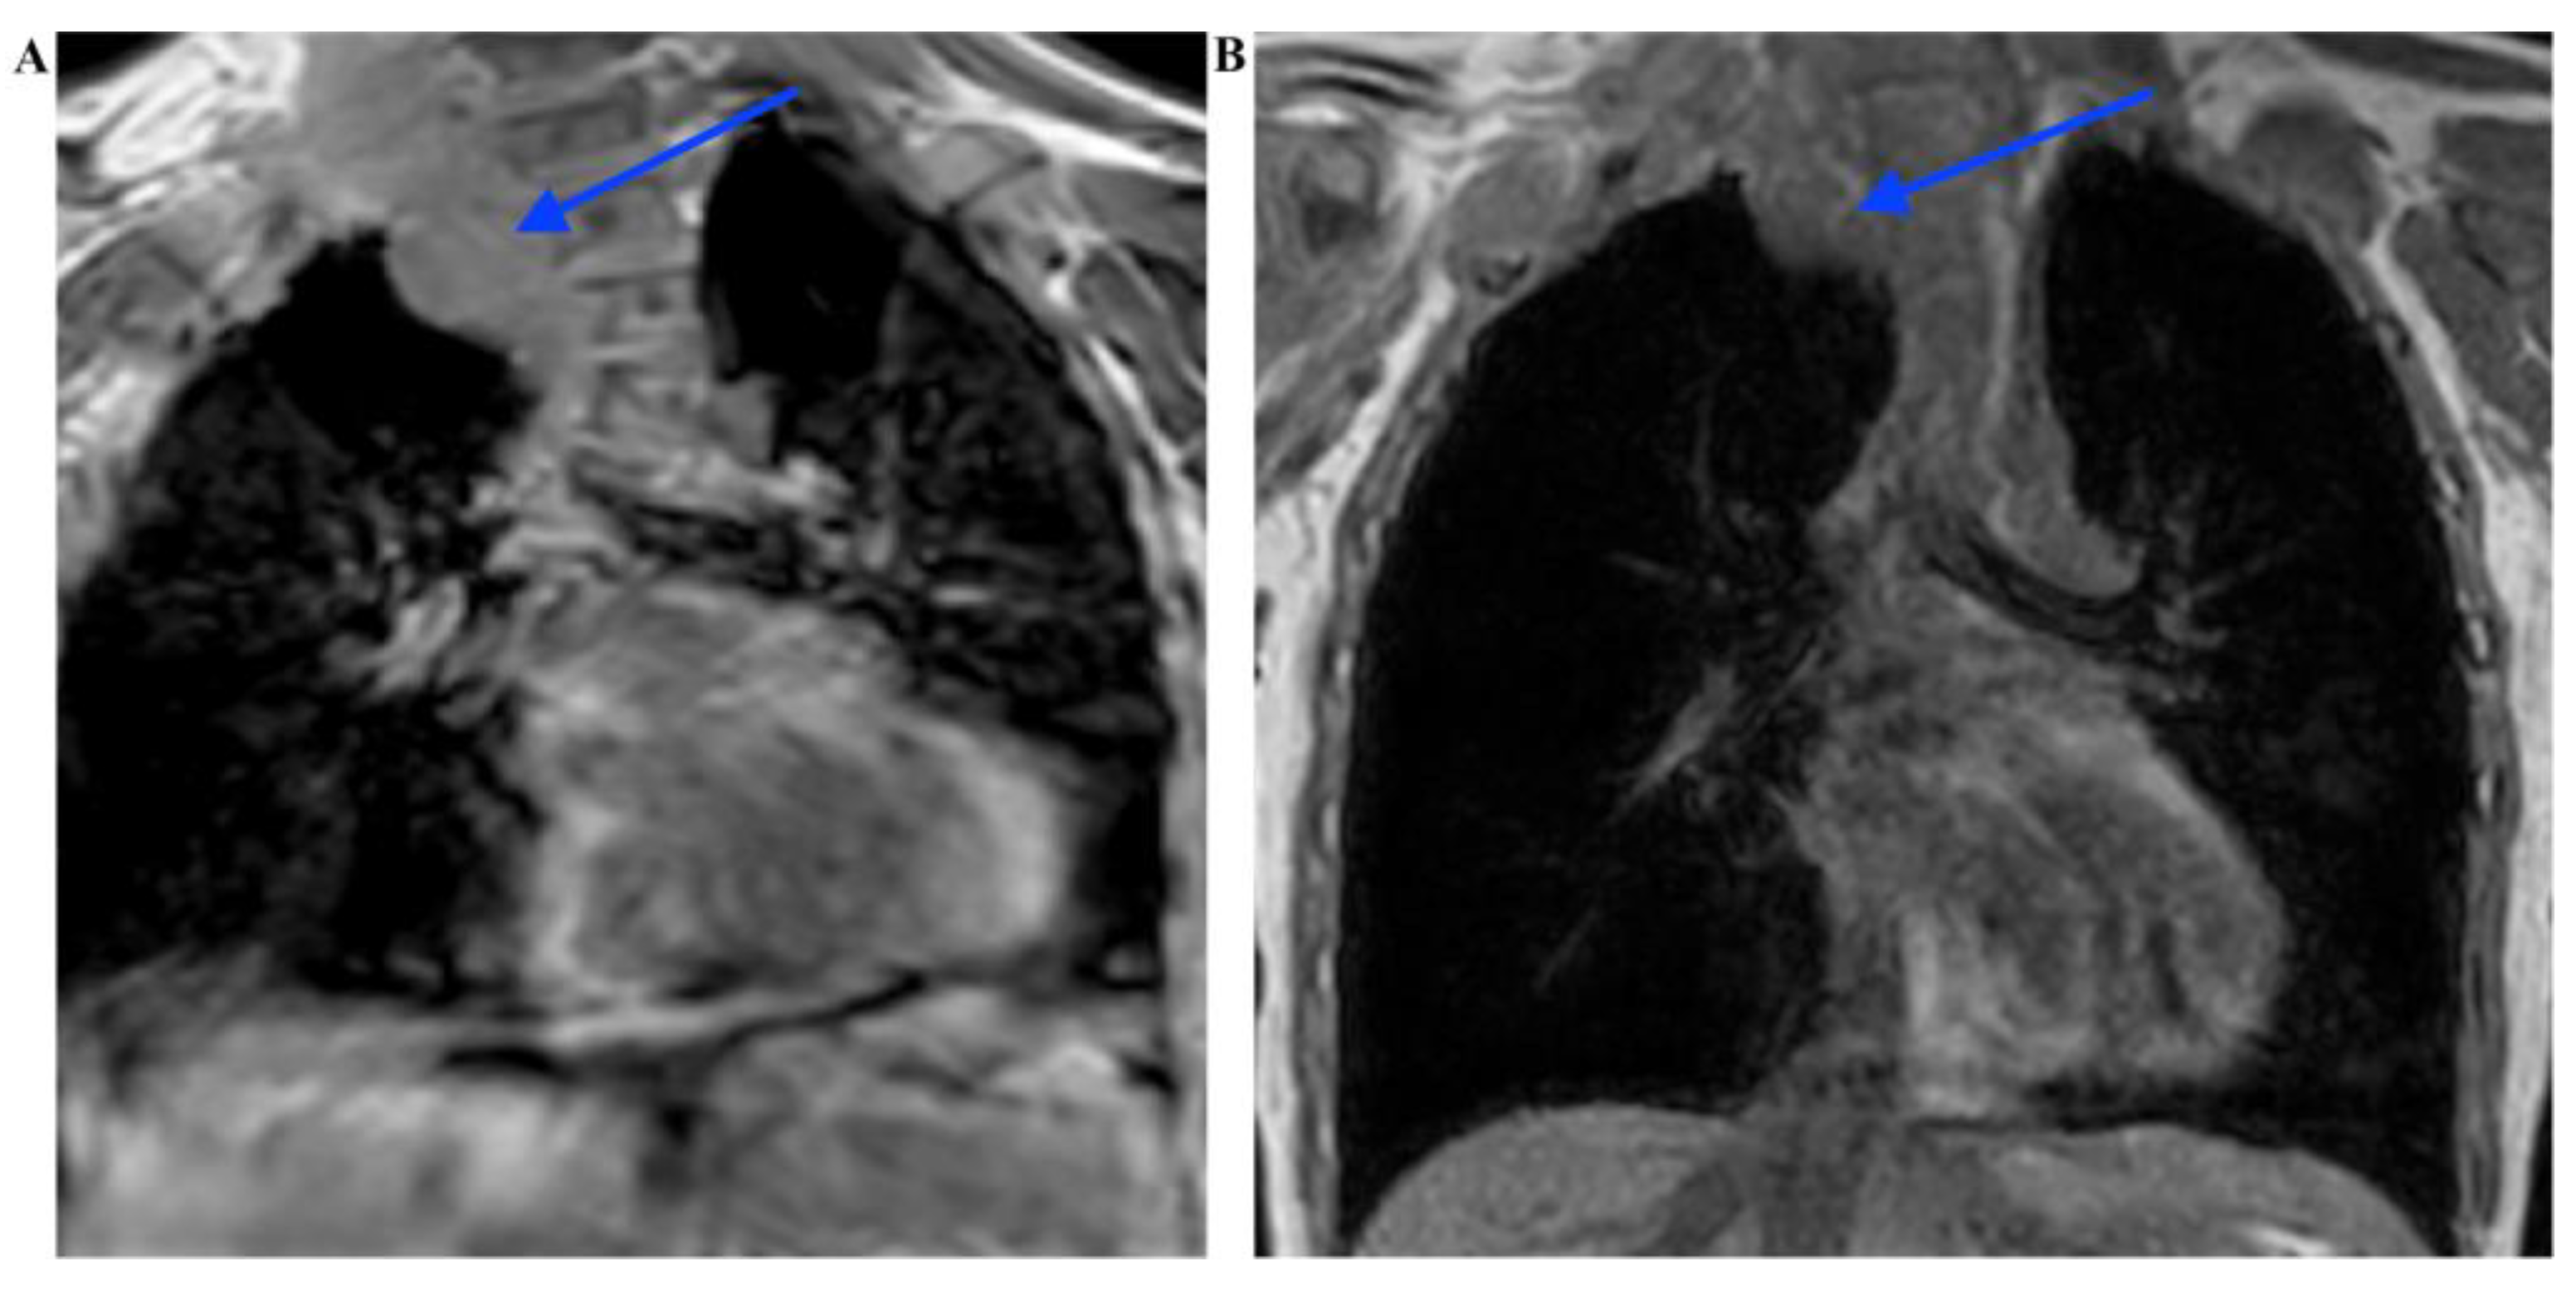

2.2. Investigation